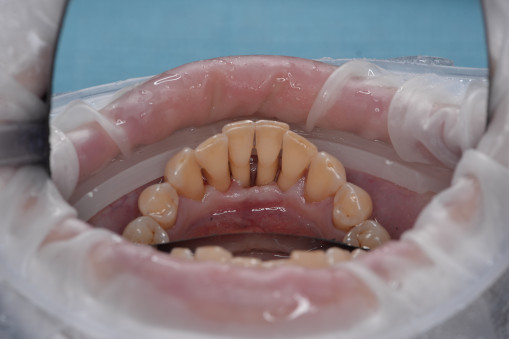

А прежде, чем вы посмотрите фотографии «до» и «после» лечения слизистой оболочки полости рта, проведенных в нашей клинике, хочу поблагодарить большое количество наших пациентов, которые поверили, прониклись нашей концепцией, и мы вместе, именно вместе победили болезни десны, гингивит и пародонтит!

До/после лечения